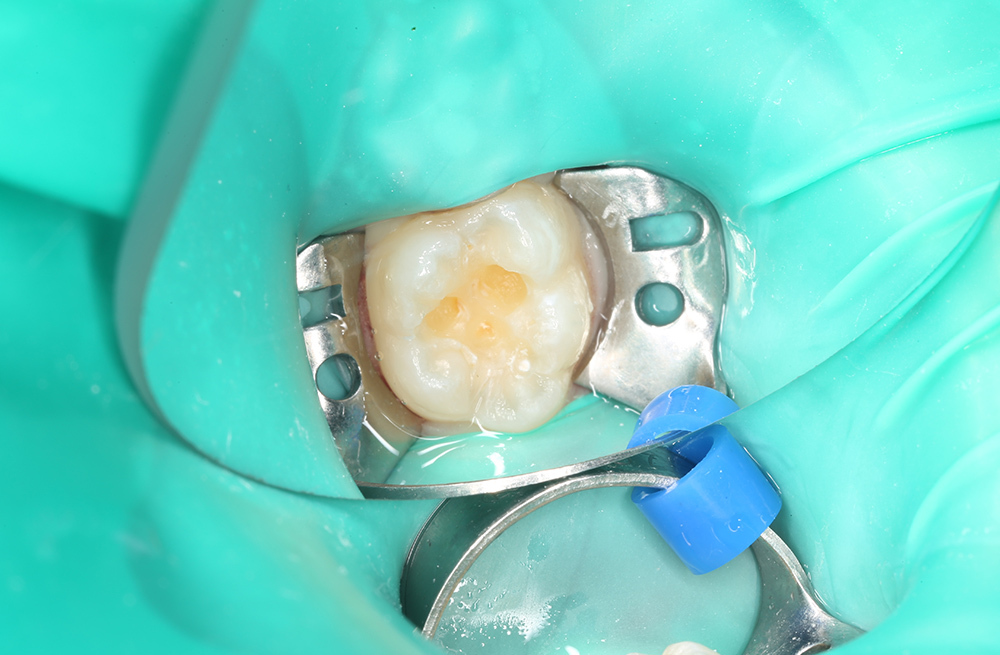

Лечение кариеса на жевательной поверхности постоянного зуба у подростка